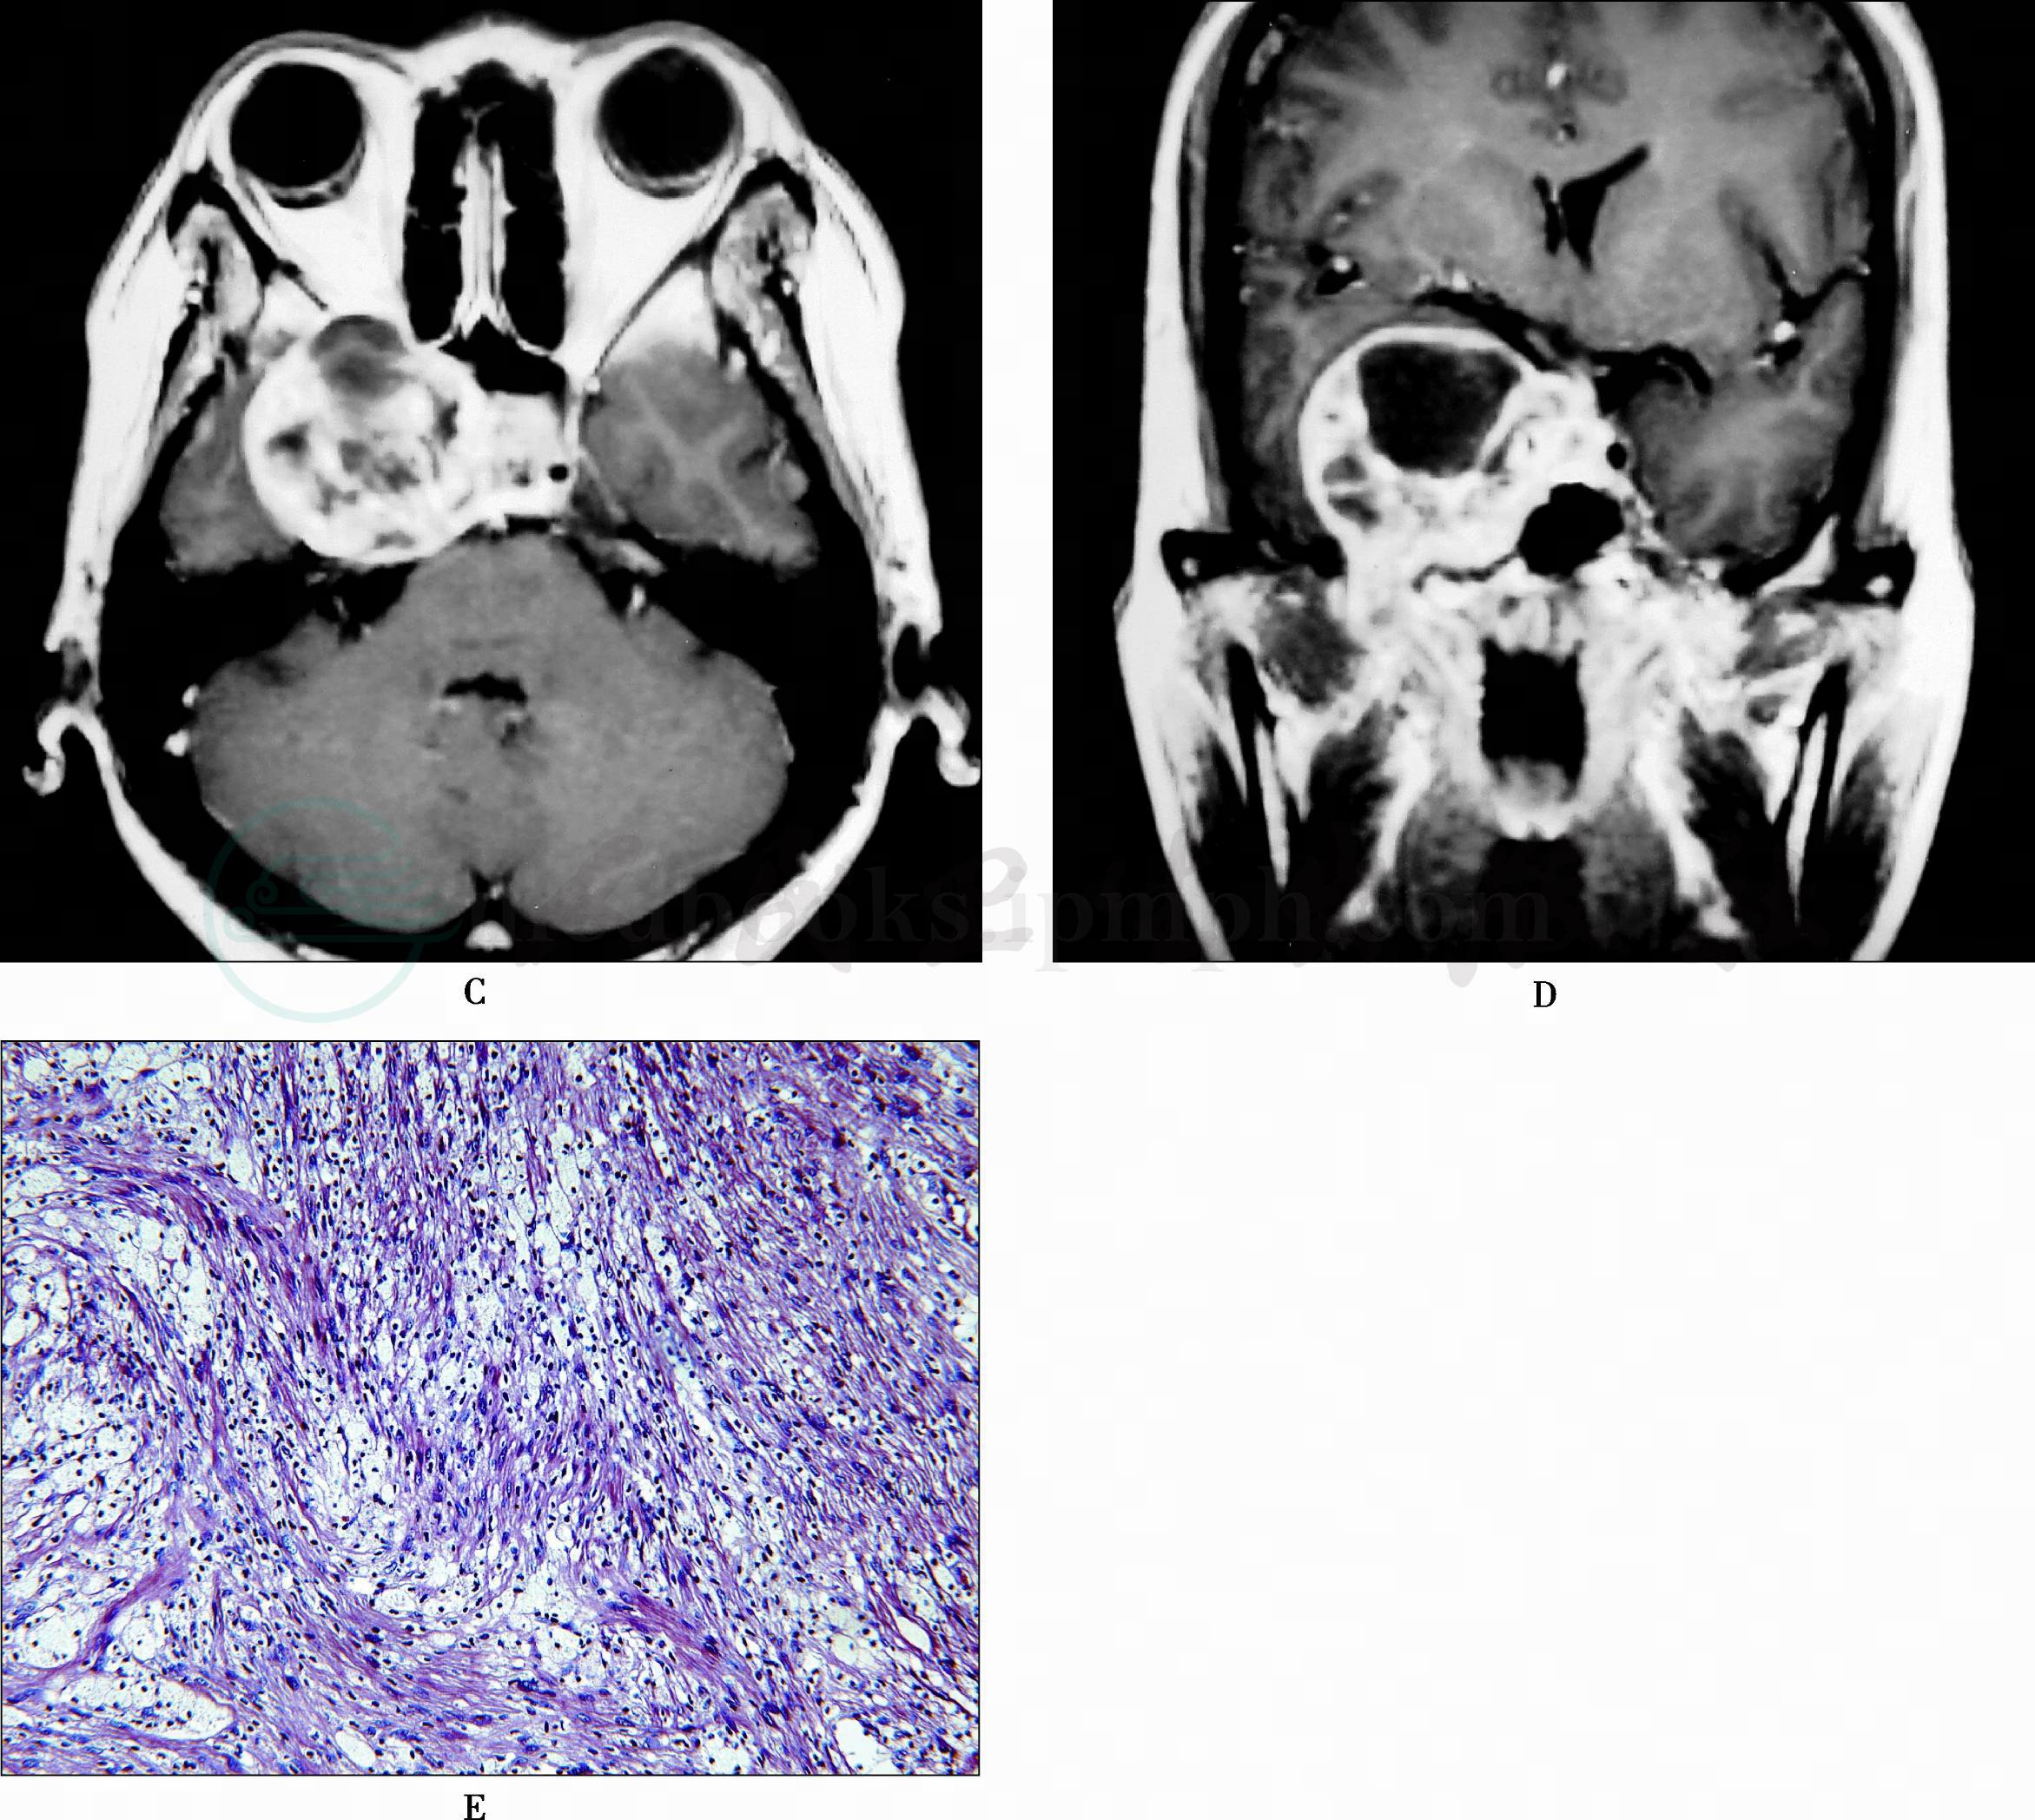

图5 右侧三叉神经瘤

A、B.轴位T1WI和T2WI示右侧中颅窝类圆形肿块,边界清晰,呈混杂长T1长T2信号;C、D.肿块不均匀强化,实性部分显著强化,中心坏死区无强化;E.病理切片:梭形瘤细胞呈平行束状或不规则旋涡状排列,瘤细胞间有黄色瘤细胞聚集